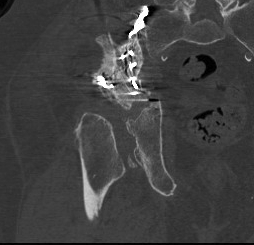

ORIF

Aim

1. Anatomic reduction

2. Provisional fixation with lag screws

3. Buttressing with curved reconstruction plates

Techniques

Posterior Column & Wall Fracture

Reduction

- often indirect

- buttress plate from Ischial Tuberosity to Ilium

- contour or use pre-contoured

- screws at plate extremities

- often 2 parallel plates if wall and column fracture

II to ensure screws not in acetabulum